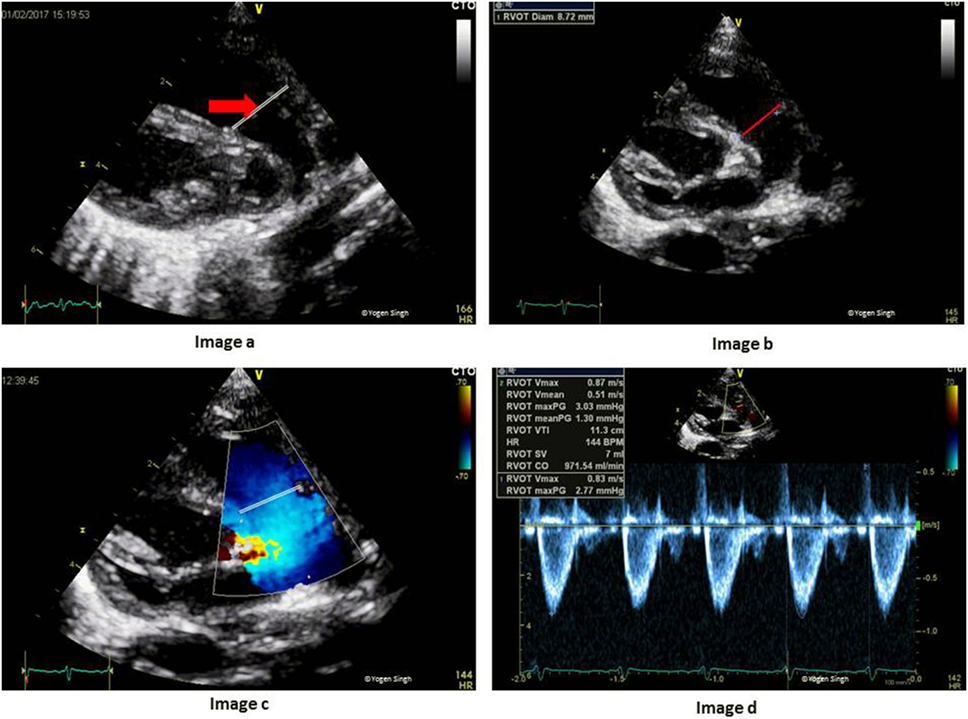

Targeted ultrasound, advanced ultrasound, level ii sonogram, fetal anomaly scan. Indeed, the feasibility of the assessment of the flow reversal was quite low in our study cohort (37.8%), which might reduce the diagnostic value of this. Other names for this test. Increased resistance in the pulmonary circuit caused by the rvot eventually leads to right ventricular hypertrophy, right ventricular failure, and eventually biventricular failure. Web however, clear visualization of the doppler signal in the pulmonary artery branches is sometimes difficult in patients after rvot reconstruction because of the ultrasound reflection at rvot. Web diagnostic radiology, ultrasound and vascular ultrasound. The depth is 2.4 cm, median speed. Web see answer (1) best answer. Web the right ventricular outflow tract (rvot) refers to the region of blood outflow from the right ventricle between the supraventricular crest and the. 4 the posterior rvot is directly anterior to the.

Web evaluating rvot (right ventricular outflow tract) with ultrasound and doppler pocus 101 18.3k subscribers subscribe 104 5.6k views 1 year ago in this. Web in untreated tof, each patient’s course is variable and depends on the severity of the right ventricular outflow tract obstruction (rvot). The depth is 2.4 cm, median speed. Web the right ventricular outflow tract (rvot) refers to the region of blood outflow from the right ventricle between the supraventricular crest and the. Web the rvot is divided into rightward (referred to as free wall), anterior, leftward, and posterior (referred to as septal) parts. Increased resistance in the pulmonary circuit caused by the rvot eventually leads to right ventricular hypertrophy, right ventricular failure, and eventually biventricular failure. Web the size and type of the most appropriate stent may be chosen, based on ultrasound measurements of the rvot, to cover the right ventricular infundibulum. Web the rvot view can be obtained by further rotation in the same direction and gentle rocking of the transducer from the lvot view. The recommendations for the assignment of relative value units (rvu's) for diagnostic. Indeed, the feasibility of the assessment of the flow reversal was quite low in our study cohort (37.8%), which might reduce the diagnostic value of this. Targeted ultrasound, advanced ultrasound, level ii sonogram, fetal anomaly scan.